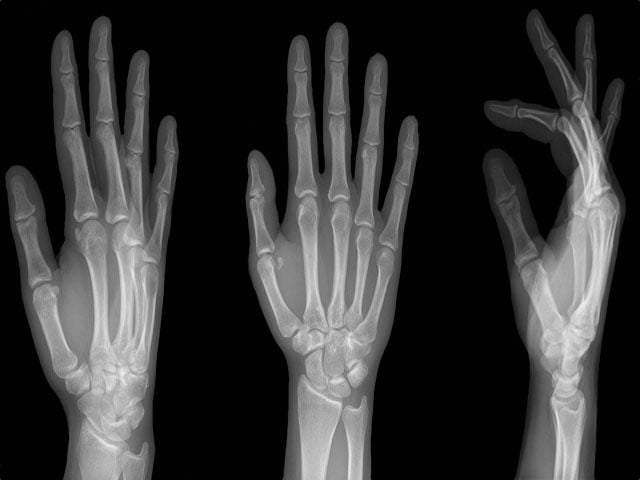

El Bilek Filmi